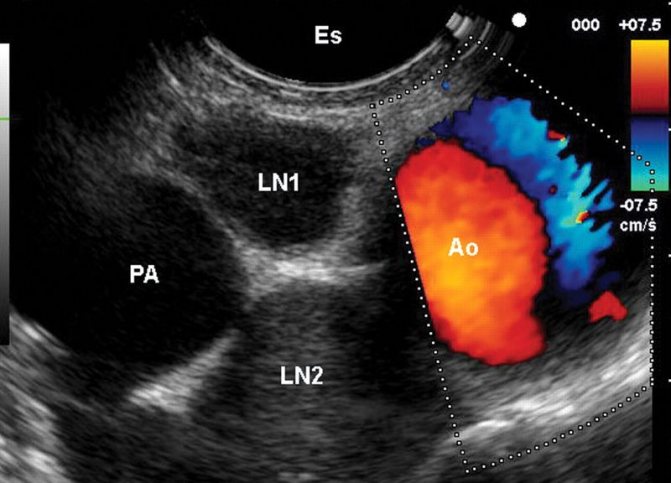

- Для визуального подтверждения количества воспаленных лимфоузлов на шее, уточнения их размеров, характера, динамики, делают компьютерную диагностику, рентген, УЗИ, томографию.

- Если выше перечисленные исследования не дают полной информации о заболевании, врач назначает биопсию лимфатического узла. Исследование тканей позволяет выявить бактерии, лимфоциты, лейкоциты и раковые клетки.